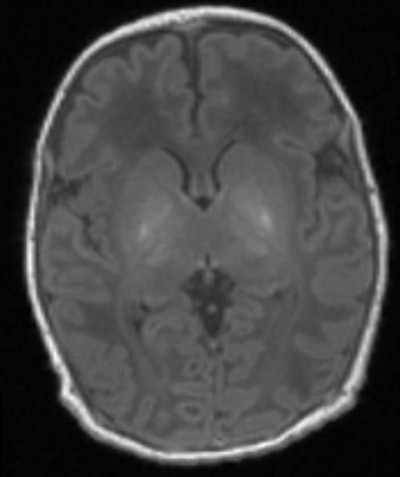

The key is MR spectroscopy's ability to measure the level of the compound N-acetylaspartate (NAA) in the baby's thalamus, which can be severely damaged by a loss of oxygen. Oxygen deprivation causes neonatal encephalopathy, which hampers brain development and neurological functions.

High levels of NAA in the thalamus indicate normal brain function, while low levels indicate brain damage. In the current study, proton MR spectroscopy predicted adverse outcomes at two years with 98% accuracy, based on initial NAA results.

To assess the value of MRS in this patient population, the researchers conducted a prospective, multicenter study between January 2013 and June 2016 in eight neonatal intensive care units in the U.K. and U.S. They included 223 term and near-term neonates who received treatment for neonatal encephalopathy. The babies underwent T1-weighted imaging, T2-weighted imaging, diffusion-weighted MRI, and thalamic proton MR spectroscopy four to 14 days after birth. MRI scans were performed on 3-tesla scanners (Philips Healthcare, Siemens Healthineers, or GE Healthcare).